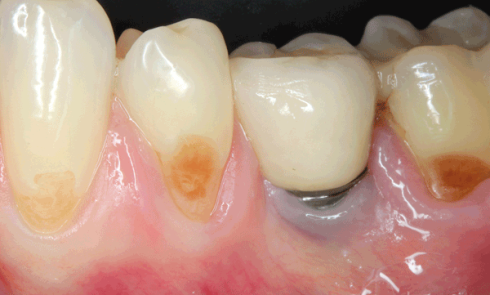

Article réservé à nos abonnés Épulis et autres tumeurs gingivales

CAS 1 Motif de la consultation. Patient de 50 ans venu consulter pour la découverte d’une tumeur gingivale lors d’une...